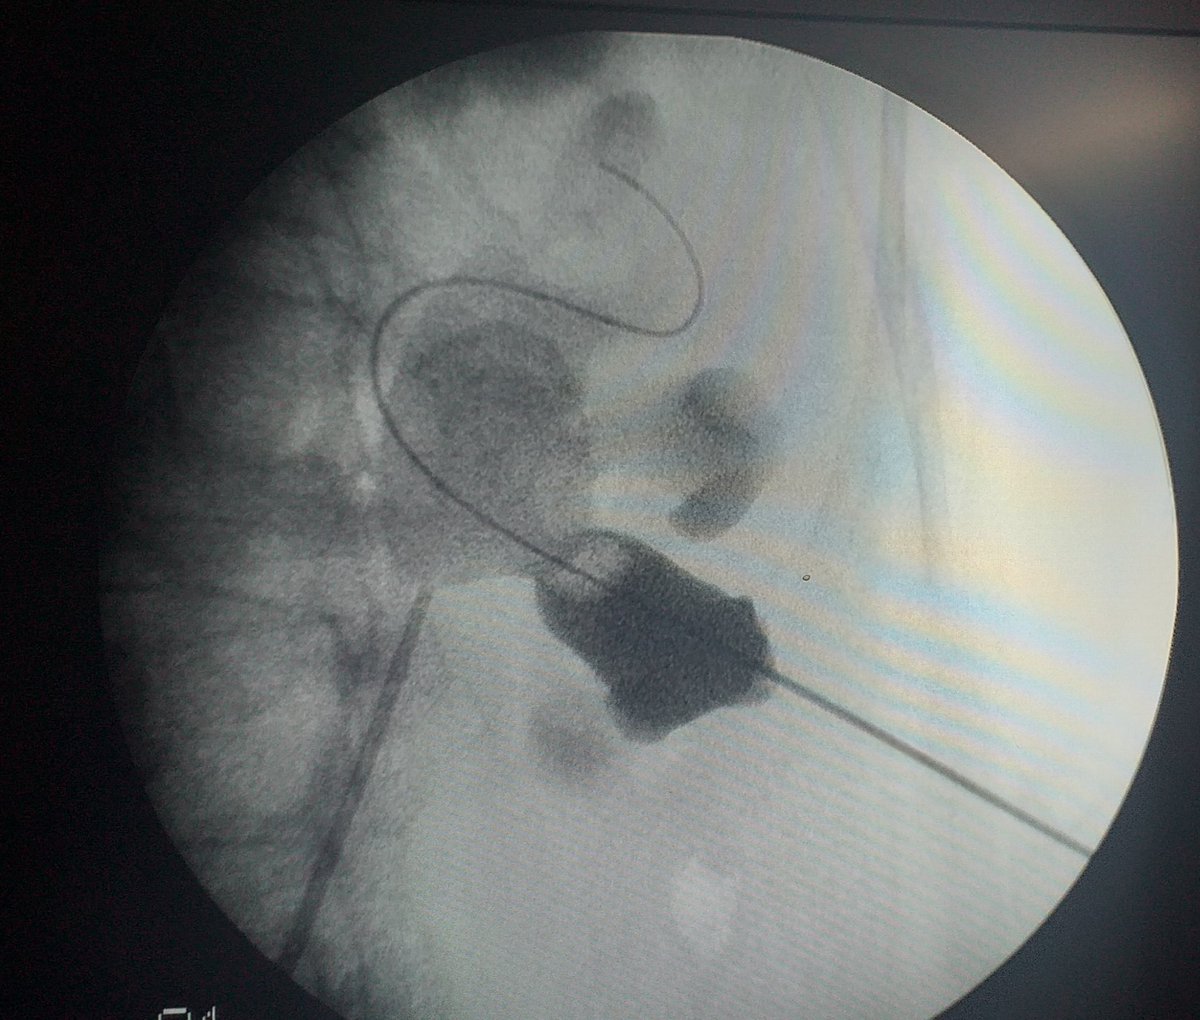

PCNL challenges

Eduardo Cruz-Nuricumbo MD Professor endourology